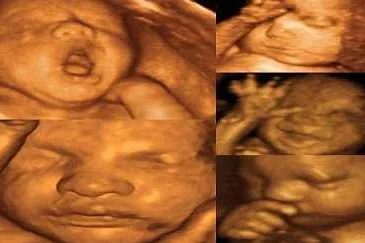

Процедура предназначена для своевременного установления патологий, определения состояния околоплодных вод, стадии развития костной массы, наличия грыж, отклонений в развитии суставов. Можно рассмотреть лицо, руки, пальцы и другие части тела ребенка.

Делают 3Д УЗИ при беременности практически так же, как и обычное ультразвуковое исследование. На ткани организма воздействуют волны ультразвука, отражаются от различных внутренних органов, а затем визуализируются с помощью специального прибора. Но при обычном УЗИ понять, что изображено на экране или распечатке, может только специалист. А вот трехмерное УЗИ лучше для родителей тем, что мать и отец получают объемное изображение, похожее на фотографию, где можно оценить внешность будущего младенца: разглядеть его личико, посчитать, сколько пальцев на руках.

3D УЗИ – это вид эхографии, при котором трёхмерная объёмная картинка формируется из двухмерных изображений. Сканирование позволяет определить пол малыша, рассмотреть его лицо и даже пальчики на руках и ногах. По сравнению с обычным двухмерным УЗИ никаких сверхвозможностей 3D-сканирование не даёт. Это не замена, а, скорее, дополнение к плановому сканированию. Но иногда объёмная картинка даёт возможность лучше рассмотреть некоторые детали. Например, на картинке можно увидеть, что лицо ребёнка сморщено. А это свидетельствует о кислородном голодании.

При проведении 4D УЗИ можно увидеть движения плода, его лицо, руки, ноги и другие детали. Это позволяет родителям узнать больше о своем будущем ребенке и создает возможность для более раннего выявления возможных аномалий и отклонений.

- 3Д изображение позволяет изучать мимику ребенка, что тоже высупает дополнительным показателем наличия или отсутствия каких-либо патологий.

- На изображении, которое получено по результатам исследования, видна мимика будущего младенца. По ней можно судить о том, положительные или отрицательные эмоции он испытывает. Отрицательные эмоции могут говорить о том, что он чувствует боль, это может быть связано с тем, что внутренние органы развиваются неправильно. Если преобладают положительные эмоции, то будущий малыш чувствует себя хорошо и причин для беспокойства нет.